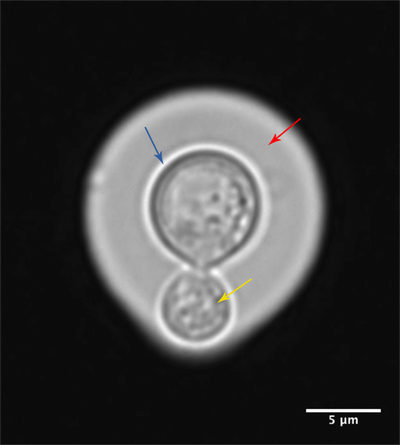

The ability of these environmental fungi to cause human infections is underpinned by a number of classical virulence factors, most notably the production of a polysaccharide capsule (Fig. 1) which protects Cryptococcus from phagocytosis, and the production of melanin pigment, which protects the fungal cell from oxidative damage. Perhaps most remarkable, however, is the ability that cryptococci have to evade immune activation.

FIG. 1. CRYPTOCOCCUS GATTII CELL STAINED WITH INDIA INK, SHOWING CAPSULE (RED), FUNGAL CELL WALL (BLUE) AND THE BUDDING YEAST (YELLOW). BAR, 5 ΜM.